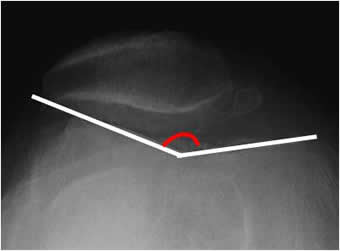

Angulo de Böhler:

Se mide con una proyección lateral de Rx. Está formado por la intersección entre las líneas que unen la parte mas superior del calcáneo, con su parte anterior y posterior. La amplitud normal está entre 20º y 40º. En casos de fracturas, el ángulo está disminuido. (Fig 90 y 91).

Fig 90. Angulo de böhler.

Rx lateral. Angulo normal.